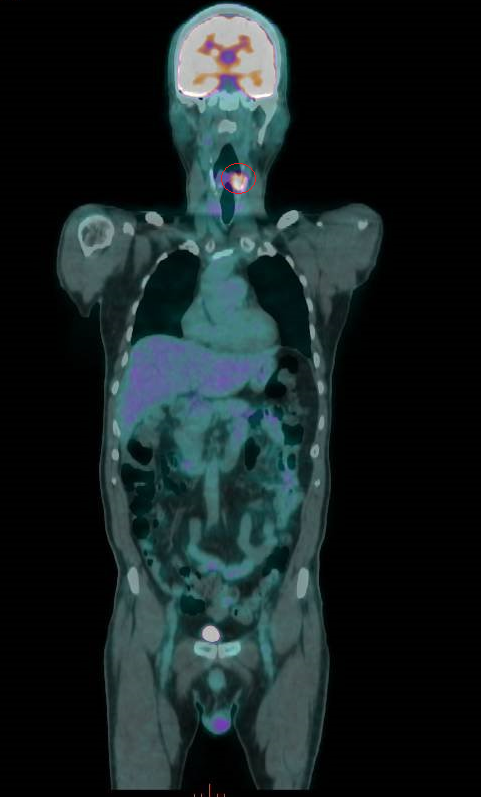

56歲的曾先生抽菸、嚼檳榔、喝酒超過30年,3年前發現下咽癌,經放射線及化學治療後,腫瘤消失,他也戒掉菸、檳、酒,沒想到在以為已熬過難關的第3年,癌症復發,最終接受全喉切除手術,失去聲帶,靠人工發聲器重新說話。

衛福部彰化醫院耳鼻喉科主任許嘉方表示,曾先生3年前喉嚨疼痛不癒,經內視鏡、電腦斷層等檢查發現,其左下咽處有個2公分的腫瘤,切片確定為惡性,是第2期癌症,不進行切除手術,採放射及化學療法,治療後腫瘤消失。

許嘉方說,過了3年曾先生復發了,同位置的腫瘤2.1公分,也是2期,經評估不適宜再進行放療及化療,只得進行全喉切除,連同聲帶一併切除,在頸部開個永久氣切孔呼吸,讓口腔只用於進食,也就是飲食及呼吸分開,至於聲音部分,使用人工發聲器。